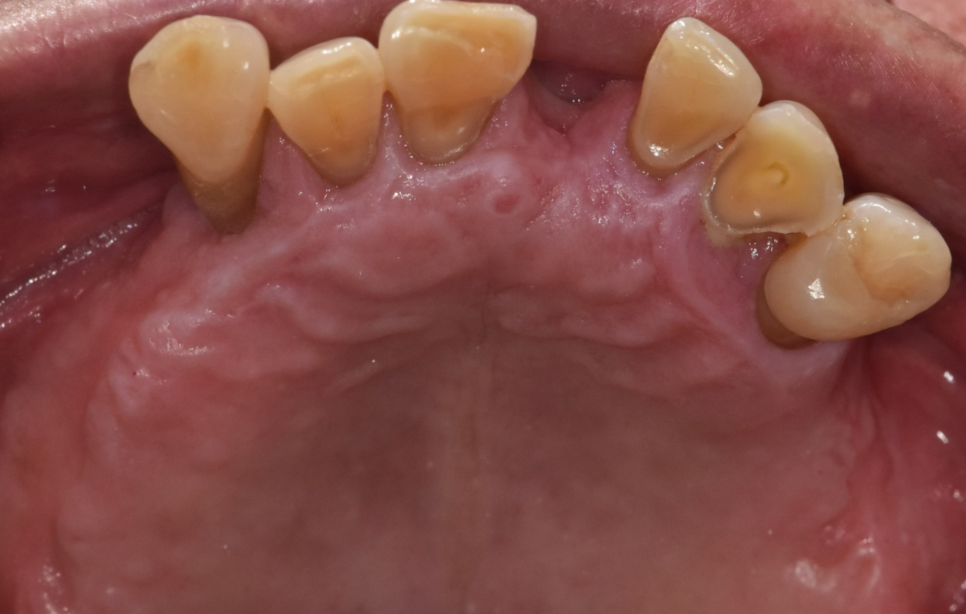

250313 1-2개 치아가 여러 치아 발치로 이어진 환자분

치아 상실 치료 2가지 방법

치아 상실 치료는 크게 두 가지입니다.